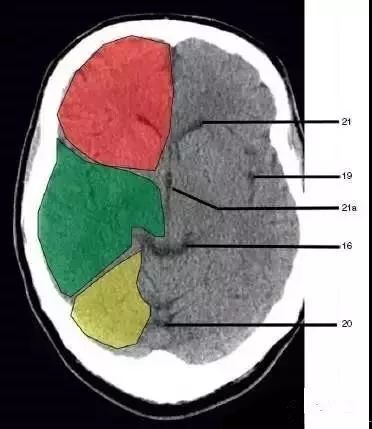

16、环池(Ambient cistern)

19、侧裂池(Sylvian fissure):绿色部分为颞叶(Temporal Lobe),浅红色部分为额叶(Frontal Lobe)

20、小脑上池(Third ventricle)

21、侧脑室前角 (Frontal horn of lateral ventricle)

21a、第三脑室 (Third ventricle):绿色部分为颞叶(Temporal Lobe),浅红色部分为额叶(Frontal Lobe),黄色部分为枕叶(Occipital Lobe)